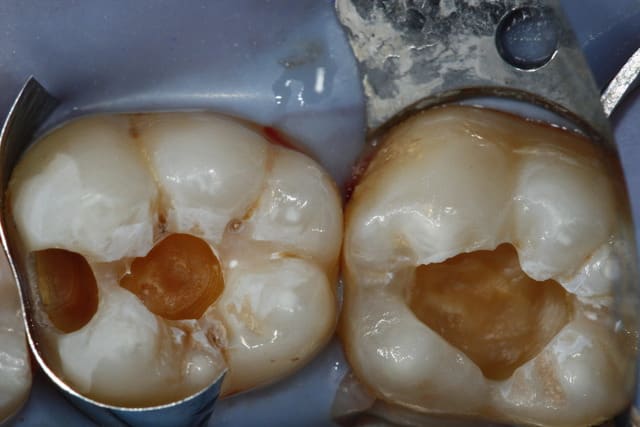

2 retraitements endo sur 45 46.

2 m85na9 - Eugenol

3 j2ewih - Eugenol

4 mbyxz8 - Eugenol

1 ojgvk3 - Eugenol